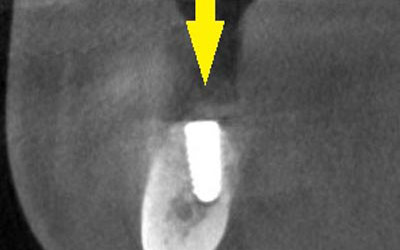

インプラントを埋入するために、骨を増やす方法はいくつかありましたが、この場合、患者様ご自身の骨をブロック状で移植するのが最も適していると判断し、自家骨移植術を行ないました。患者様ご自身の下顎前歯の下方から骨を採取して、骨がなかった部位に移植し、スクリューで固定したCT画像です。黄色矢印部分が、2つの骨片を移植して、固定したところです。

-

手術後の、別な方向からみたCT画像です。術前に大きく吸収されていた部分に、骨のブロックが移植され、骨が造成されています。真っ白にピンのように写るのは、骨を固定した小さなスクリューです。